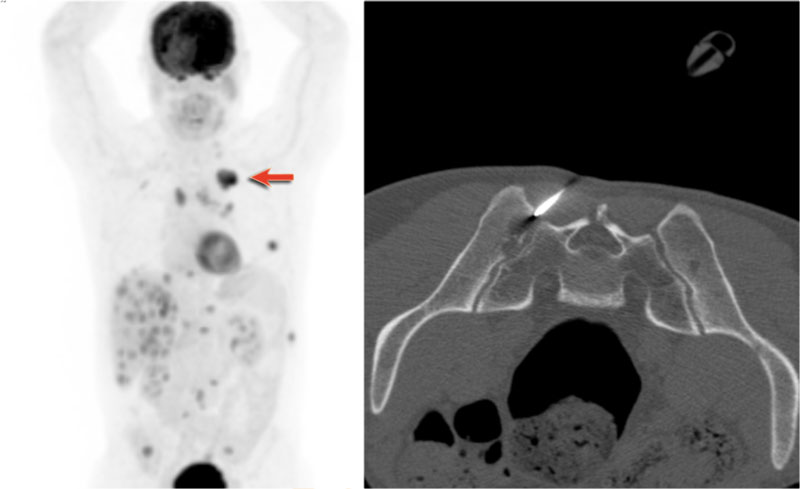

Hidden area (5): Mass Behind the First Rib

In some patients, an accessory joint at the anterior aspect of the first rib may simulate a mass, as we learned earlier.

However this area is also a "hidden zone", where true lesions can be masked.

• In this case, a small lung carcinoma was obscured by the left first rib on the PA view.

• On the lateral film, the lesion is visible in the retrosternal space.

Continue with the PET-CT...

Subsequent PET-CT imaging confirmed a hypermetabolic tumor (arrow), with metastases to the bone and liver.

• Diagnosis was confirmed via biopsy of an osteolytic metastasis in the iliac bone.